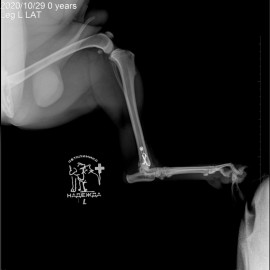

Рентгенологические снимки до операции.